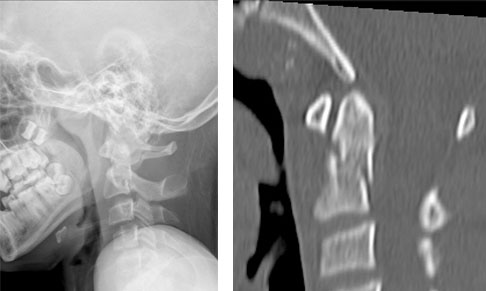

病例1  寰椎陈旧性旋转脱位,后路寰枢椎椎弓根螺钉复位融合术。

患儿8岁10月,女性,寰枢椎陈旧性旋转脱位。

患儿入院时头颈歪斜畸形,旋转活动受限明显

患儿术后头颈歪斜畸形即刻恢复正常,四肢肌力、感觉正常。

术前患儿头颈部歪斜畸形,术后头颈部恢复中立位。